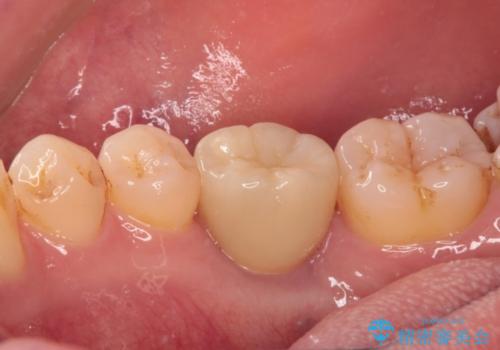

- 大学病院でインプラント治療を進めていたものの、予約のタイミングが合わないとのことで来院された患者様です。

欠損部位の骨や歯肉の状態は非常に良く、速やかにインプラント埋入を行い、補綴治療を進めて行くことのできる状態でした。